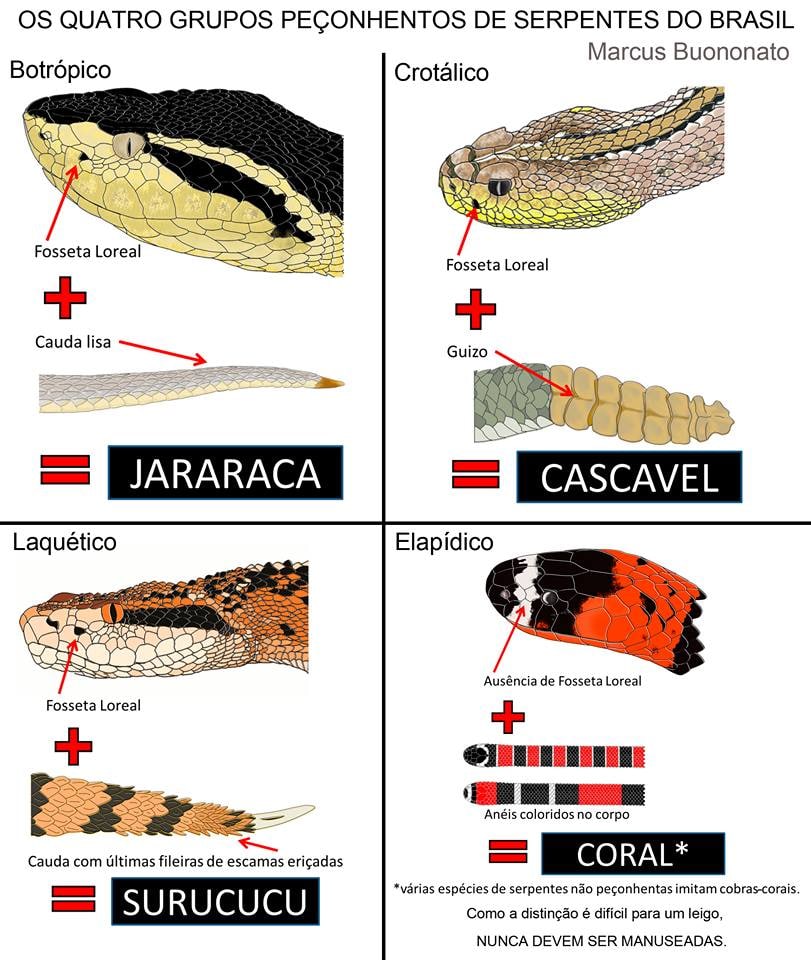

Jamais capture a serpente para levar até o centro hospitalar, a equipe médica não é treinada para identificar serpentes, podem se assustar, e além disso, outra pessoa pode se acidentar. Para registrar com qual serpente ocorreu o acidente, tire uma foto e observe bem as características dela (se possível), caso não consiga, geralmente o acidentado é medicado de acordo com os sintomas derivados de cada tipo de veneno de cobra.

— Fotografar ou registrar características marcantes da serpente para ajudar na identificação

Procure registrar de alguma forma as características da serpente do acidente, pode ser por meio de uma fotografia (tirada de uma distância segura) ou até observar as características dela, na próxima seção relembraremos as características marcantes das cobras peçonhentas que devemos ter cuidado no Brasil.

Existem 05 soros produzidos para acidentes ofídicos, são eles:

- Soro Antibotrópico;

- Soro Antibotrópico e Antilaquético;

- Soro Anticrotálico;

- Soro Antibotrópico e Anticrotálico;

- Soro Antielapídico;

Achou os nomes familiares? Isso é devido cada soro ser específico para a peçonha da família ou gênero da cobra peçonhenta! Além disso, existem soros que combatem as toxinas de mais de uma família ou gênero de serpentes, tendo ação dupla.